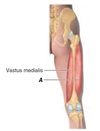

What is the innervation of muscle A?

Femoral nerve (L2, L3 and L4)

A - Vastus medialis

Name muscle A

A - Vastus medialis

What is the innervation of muscle A?

Name muscle A

A - Vastus medialis